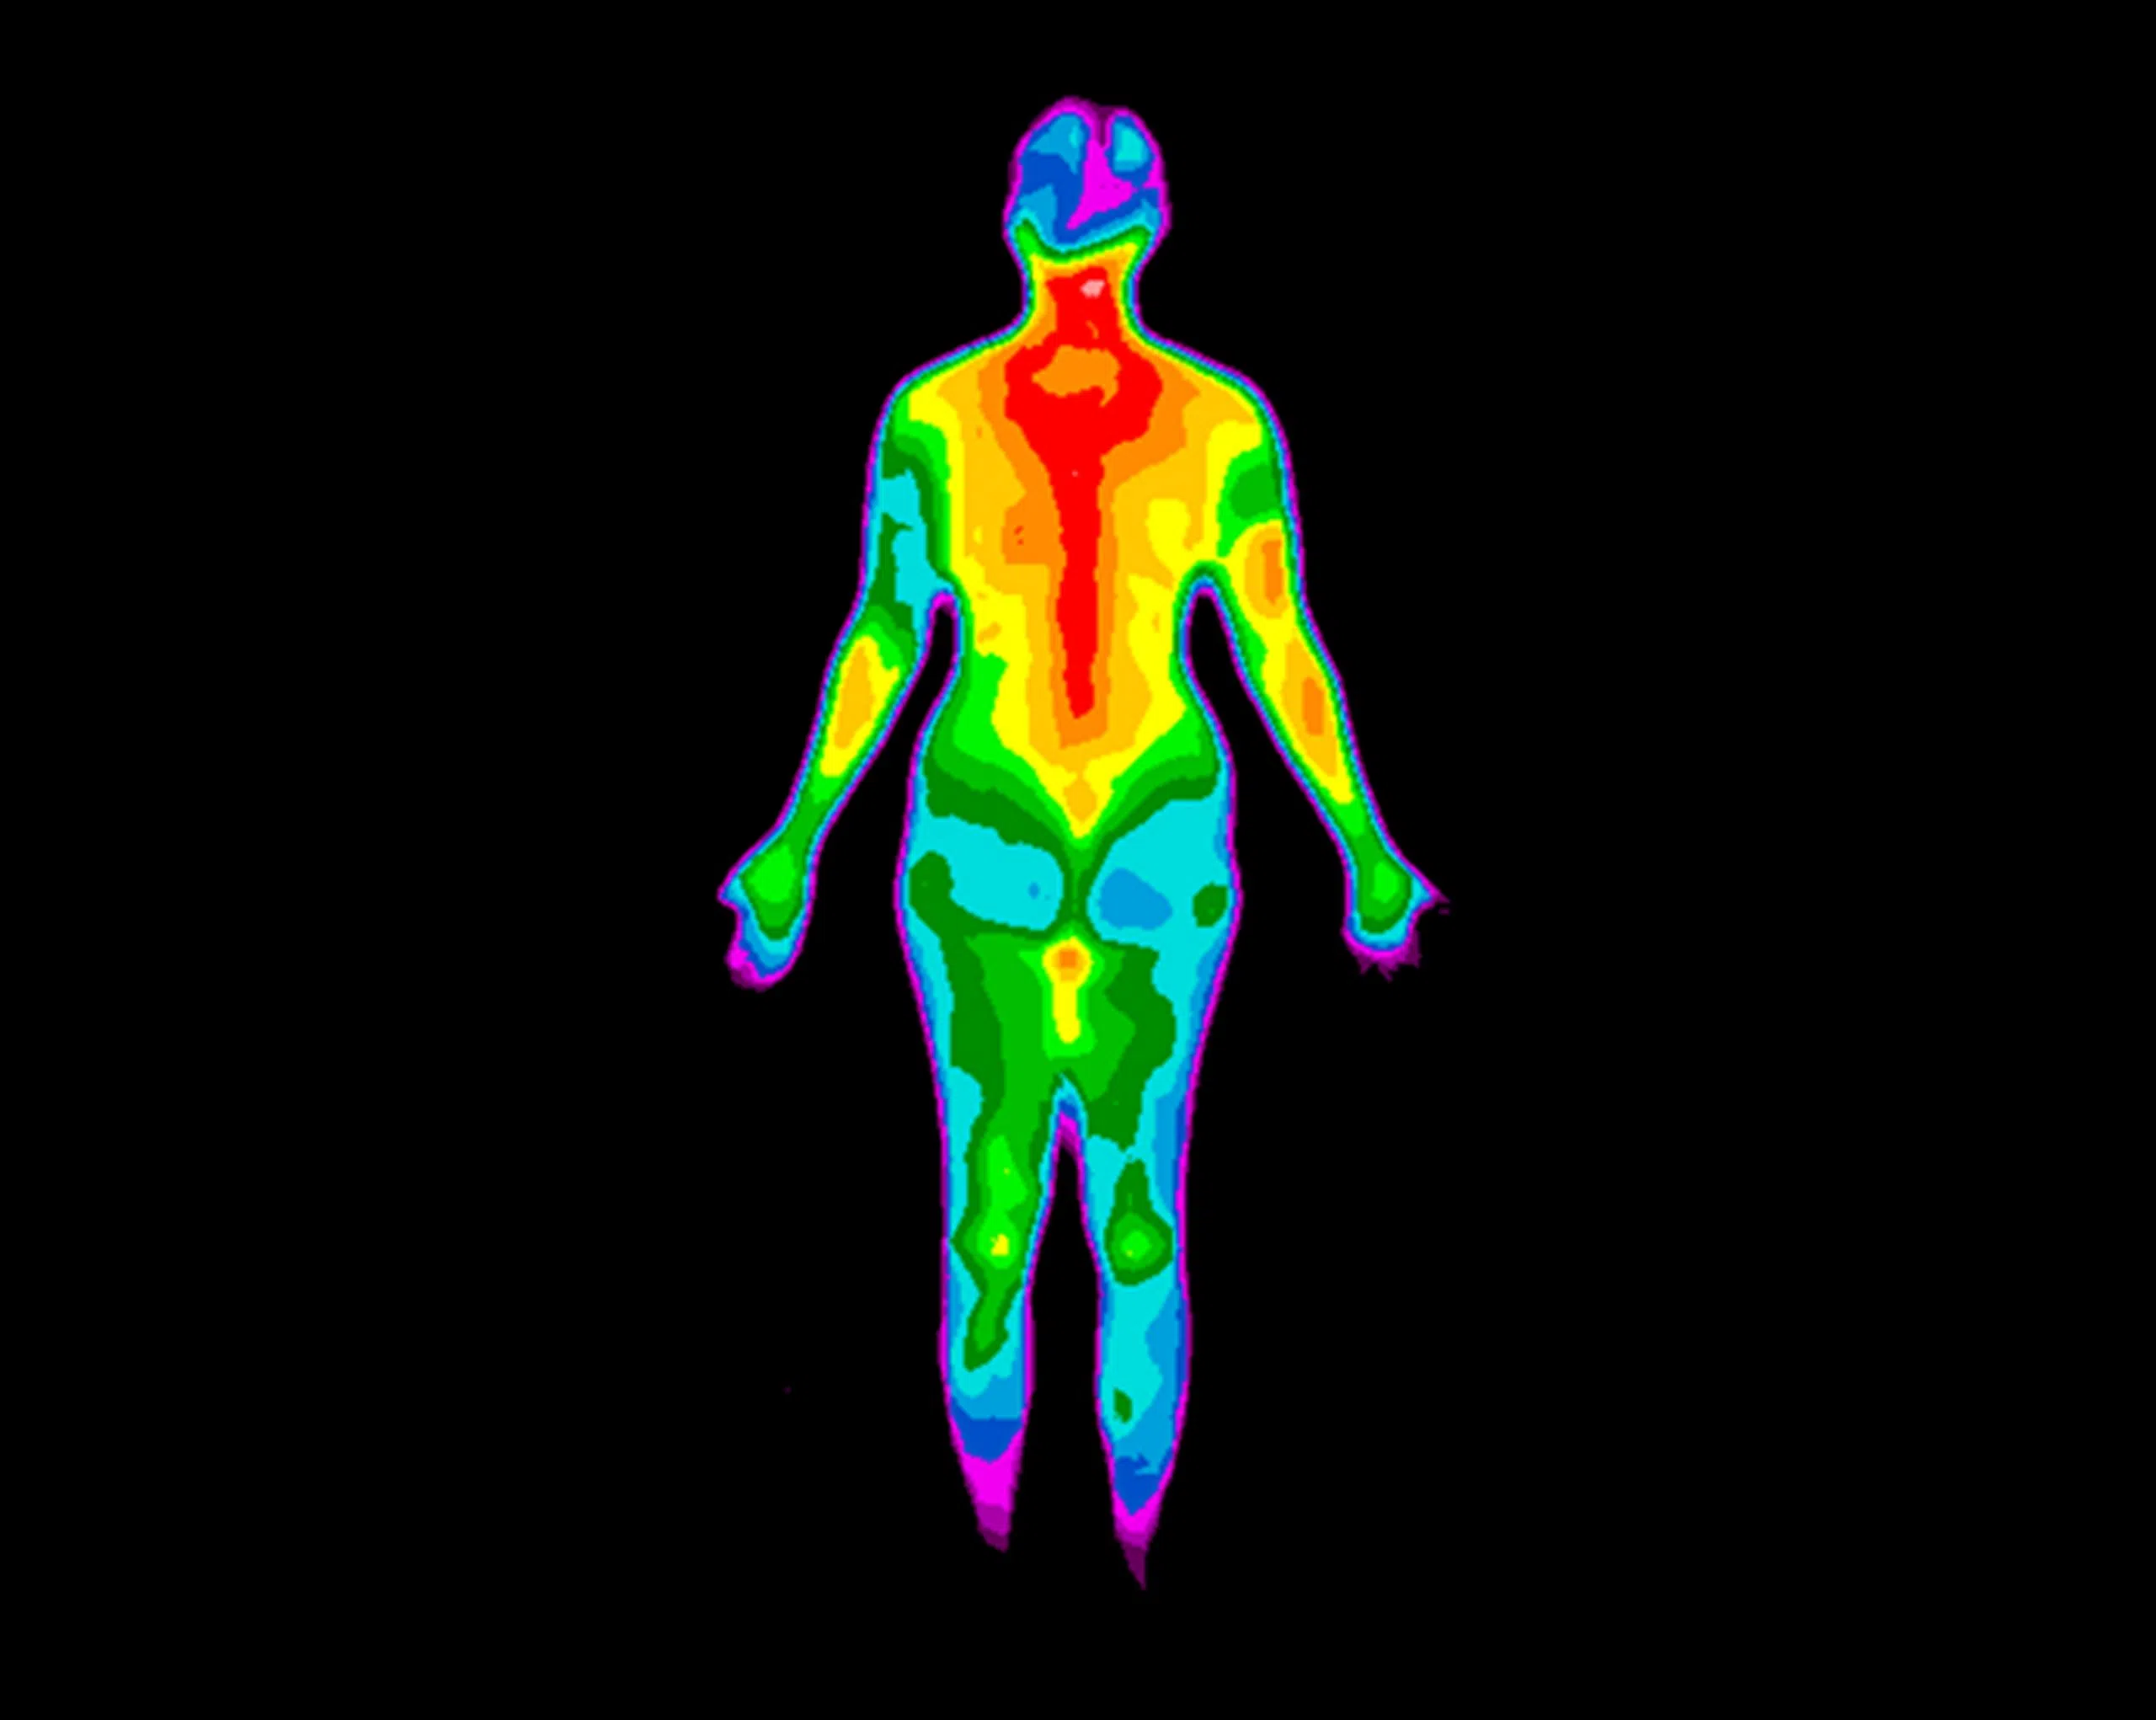

Los Angeles International Airport will start testing thermal scanning cameras to detect travelers who may be sick with coronavirus. Mayor Eric Garcetti says this is an additional layer of public health protection and will not be used in place of screening travelers. Garcetti says their will be posted signs at LAX letting people know where the pilot program is going on. The cameras will detect passengers with a body temperature of 100-point-four degrees or more. If a traveler is detected to have fever they will receive a second screening by a medical professional.